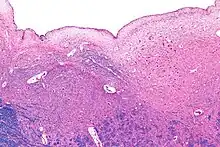

Micrograph of the posterior portion of the open part of the medulla oblongata, showing the fourth ventricle (top of image) and the hypoglossal nucleus (medial - left of image) and the dorsal motor nucleus of the vagus nerve (lateral - right of image). H&E-LFB stain.